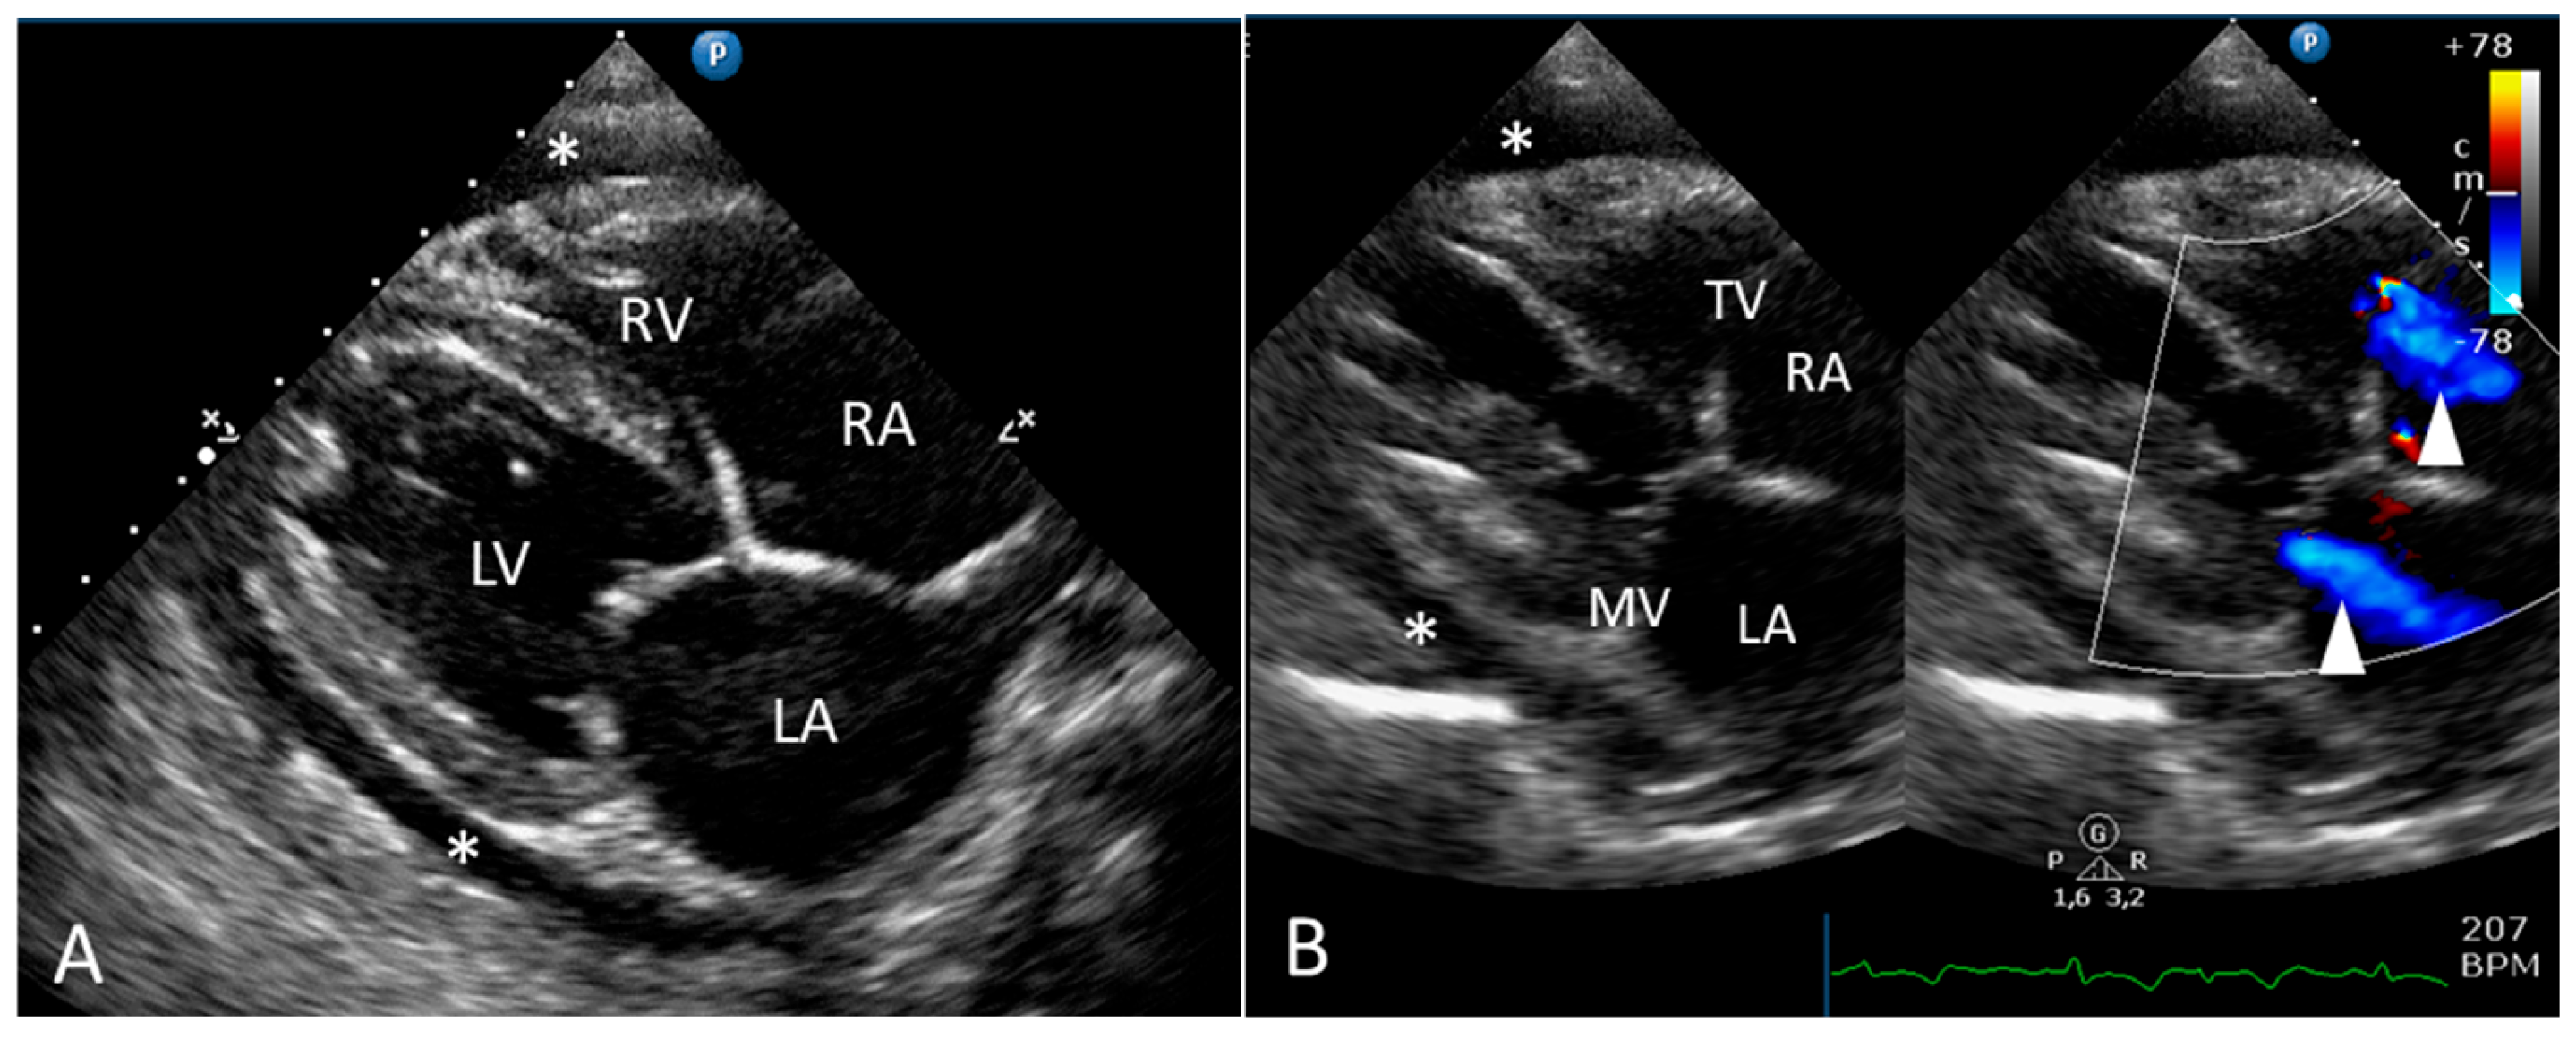

2.1. Clinical Report